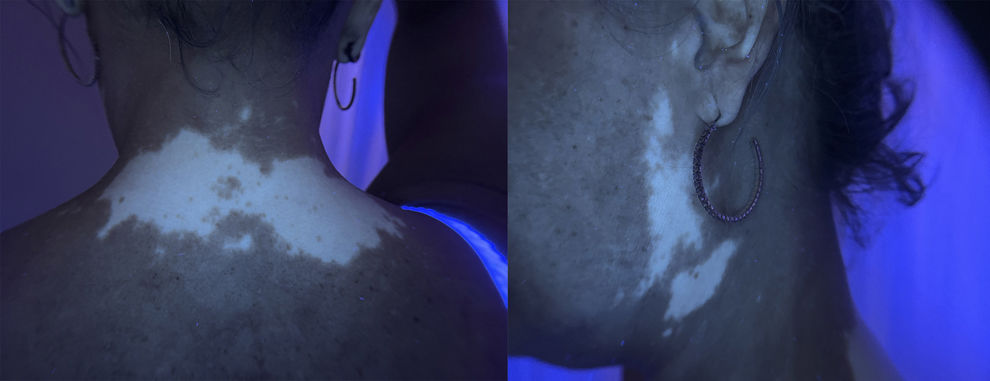

Physical examinationExamination revealed acral macules with well-defined borders located on the posterior neck, as well as periocular, frontal, and preauricular regions of the face (Figs. 1 and 2). The lesions became more evident under Wood's lamp examination (Fig. 3).

DiagnosisRibociclib-induced vitiligo.